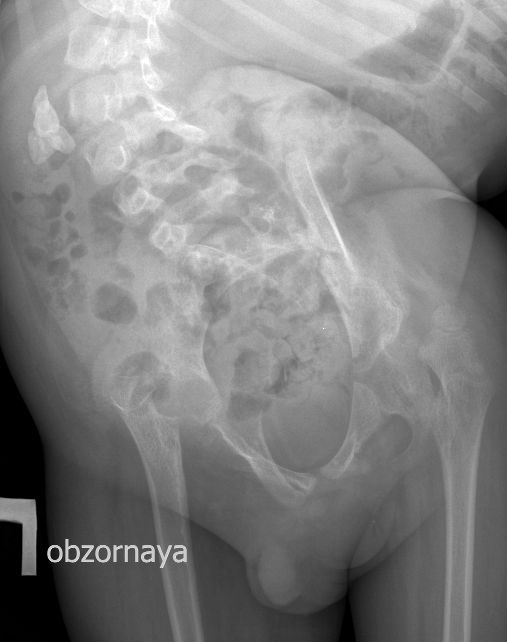

Для того, чтобы продемонстрировать степень ортопедических проблем и облегчить задание (или усложнить :) ) добавляю обзорную рентгенограмму брюшной полости

DX0001.jpg

Нейрогенный мочевой пузырь (?), МКБ, конкремент мочевого пузыря, двухсторонний мегауретер, конкремент правой почки.

Ребёнок 4-х лет с терминальной гидроцефалией (объём мозгового черепа около 6 - ти литров на глаз), тетрапарезом, вторичным сколиозом 4-й степени, двухсторонним вывихом тазобедренных суставов, глуьокой умственной отсталостью поступил в детское хирургическое отделение. Мать отмечает в течение последних 2-х месяцев кровянистые выделения на памперсе, в последние несолько недель беспокойство ребёнка. В анализе мочи - гематурия.